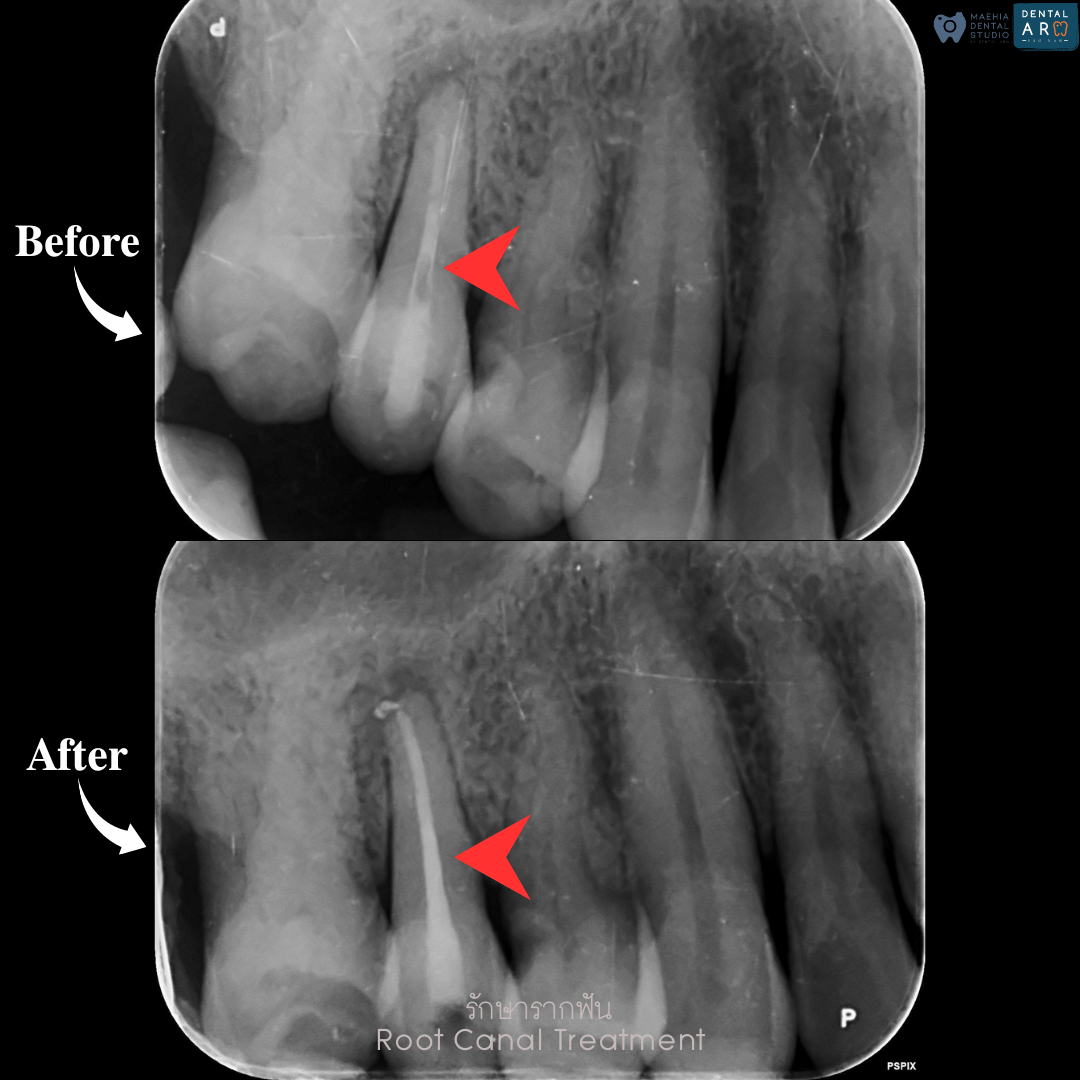

รักษารากฟัน

คือ การรักษาฟันที่เกิดการอักเสบและติดเชื้อภายในโพรงประสาทฟัน และเนื้อเยื่อรอบปลายรากฟัน อันมีสาเหตุมาการอักเสบและติดเชื้อภายในรากฟัน โดยทันตแพทย์จะทำการทำความสะอาดและใส่ยาในคลองรากฟัน และทำการอุดรากฟันเป็นขั้นตอนสุดท้าย การรักษารากฟันจะช่วยเก็บรักษาฟันให้สามารถคงอยู่ในช่องปากต่อได้ โดยไม่ต้องถอนฟันและไม่ต้องใส่ฟันทดแทน